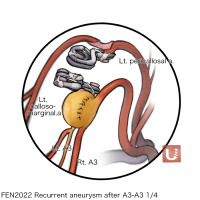

FEN2022シリーズ